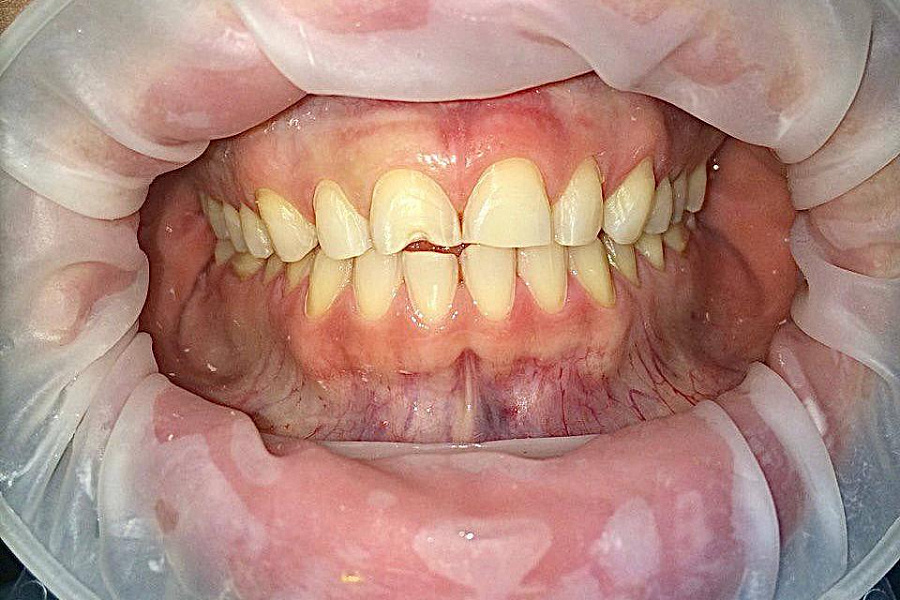

С какой проблемой обратился пациент

• выраженная стираемость зубов

• поврежден край переднего зуба семечками

В первую очередь был запрос на эстетическую часть. Пациентка хотела, чтобы новые зубы выглядели естественно.